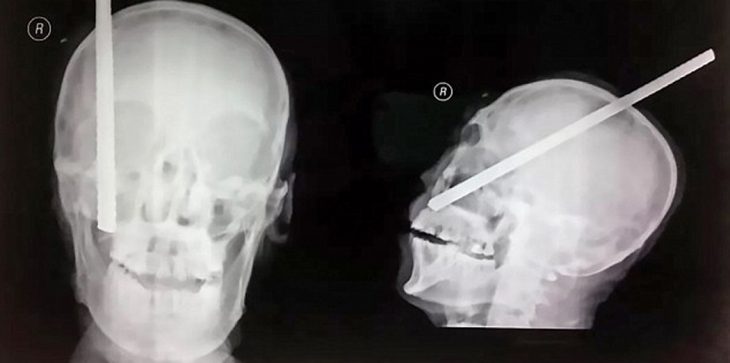

تمكن عامل بناء في الصينيدعى “كانغ جي”من النجاة بعد اختراق سيخ حديدي لرأسه، حيث سقط السيخ الذي يبلغ طوله 3 أمتار (10 أقدام) من ارتفاع عالي ودخل في رأس الرجل البالغ من العمر 56 عاما والذي لم يكن يرتدي خوذة السلامة.

وتمكن المسعفون من نقل كانغ إلى مستشفى محليأولاً في قانسو لإجراء فحص بالأشعة المقطعية قبل نقله إلى مستشفى أكبر في مدينة شيآن، حيث دخل السيخ إلى جمجمة الرجل من الجانب الأيمن واستقر في دماغه بعمق حوالي 20 سم (7.8 بوصة) بحسب المستشفى.